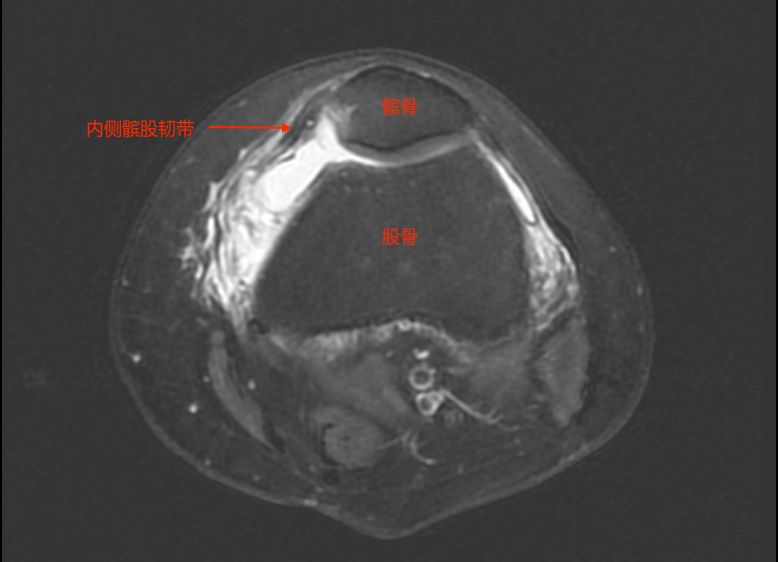

造成复发性髌骨脱位的因素众多,其中,内侧髌股韧带是导致复发性髌骨脱位的主要因素。经检查,汤女士内侧髌股韧带断裂了。

内侧髌股韧带是限制髌骨向外侧滑移的稳定结构。当此韧带损伤时,髌骨就可能发生脱位或者半脱位,引起膝关节肿胀、疼痛及活动受限,严重时还可引起髌股关节面软骨及膝关节内其它结构损伤。

汤女士初次受伤时左膝关节MR提示

内侧髌股韧带自股骨端撕脱